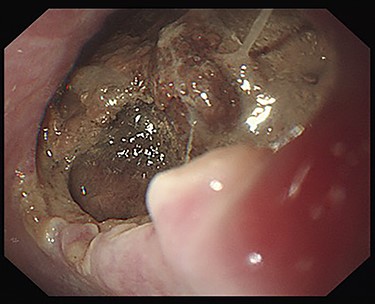

Seven days after TEVAR, the patient developed fever, and a CT scan showed bilateral iliopsoas abscesses and gas images inside the aneurysm (Fig. 2). We decided to perform upper gastrointestinal endoscopy and CT-guided drainage for abscesses. Endoscopy showed perforation of the esophageal wall and accumulation of necrotic tissue (Fig. 3).

Esophagoscopy revealing an aortoesophageal fistula covered by necrotic tissue.